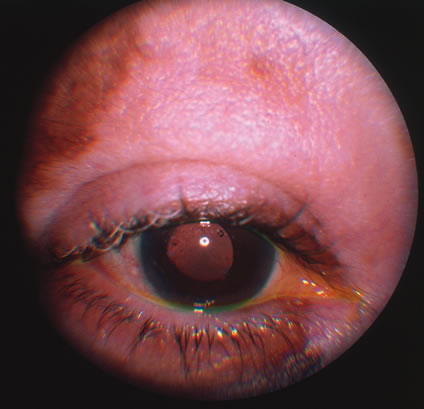

In primary ocular HSV infections, a severe follicular conjunctivitis with regional adenopathy is present. Vesicles may appear on the eyelid skin or lid margin, producing blepharitis (Fig. 3). Corneal involvement initially takes the form of a superficial punctate keratitis, which may progress to dendritic or geographic ulceration. Stromal infiltrates and uveitis are less common and relatively mild in primary disease. In uncomplicated cases, lesions usually heal completely in 2 to 3 weeks without scarring. Most cases of ocular HSV are recurrences. Recrudescent ocular herpes may take the form of dendritic or geographic ulcers, recurrent erosions, interstitial or disciform stromal keratitis, and anterior uveitis.3 HSV may also be an agent of retinitis and acute retinal necrosis (Fig. 4).

Fig. 3. Lesions of herpes simplex virus (HSV) type 1 on the surface of the eye after topical fluorescein administration.